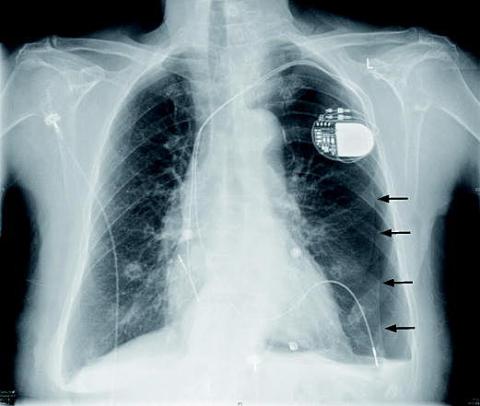

En 89-årig kvinde blev indlagt på grund af stikkende brystsmerter. Der var ingen sikker effekt af nitroglycerin. Patienten havde to måneder tidligere fået anlagt en pacemaker på indikationen intermitterende tredjegradsatrioventrikulært blok. Ved en rutinerøntgenundersøgelse af thorax sås der på det tidspunkt ingen påfaldende forhold.

Elektrokardiografi ved indlæggelsen viste sinusrytme med pace-spikes og exitblok. På grund af de atypiske smerter blev der taget et nyt røntgenbillede af thorax. Billedet viste en venstresidig pneumothorax udløst af en pacemakerelektrode, der havde arbejdet sig igennem højre ventrikels væg og ind i venstre lunge. Patienten blev overført til et center med invasiv funktion til ekstraktion af elektroden og anlæggelse af pleuradræn.

Ved enhver patient med uafklarede brystsmerter bør akut røntgenundersøgelse af thorax indgå i diagnostikken. Undersøgelsen er billig, hurtig og noninvasiv.